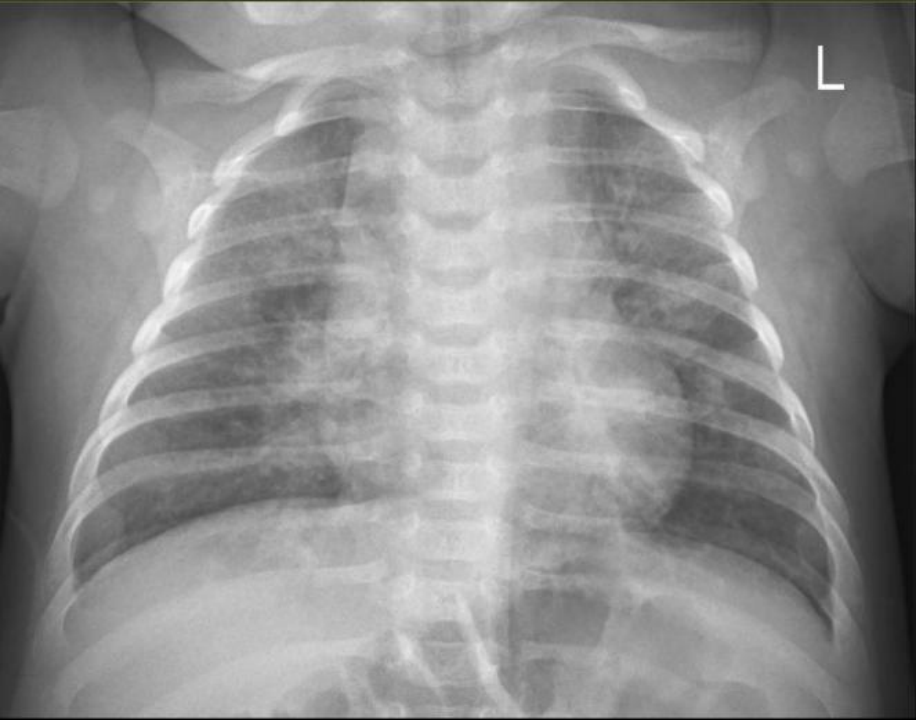

CT肺炎的大部分患儿早期都表现为双眼分泌物增多等结膜炎症状,病初只有轻微呼吸道症状(鼻塞、流涕),后逐渐加重,大多数无发热,表现为反复的短促咳嗽、呼吸急促。胸部X线检查常显示肺部过度充气和弥漫性肺间质浸润,血中嗜酸性粒细胞常增多。

CT肺炎胸片